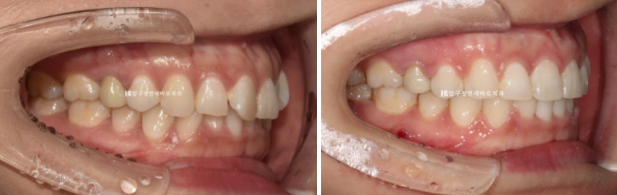

23.04~24.10

작년 4월 돌출과 덧니 때문에 찾아오신 30대 환자분입니다.

지방에서 오신 분입니다.

윗니 아랫니가 깊게 물리는 과개교합, 덧니, 중심선 불일치가 보입니다.

23.04

앞니 배열이 삐뚤합니다.

옆모습 분석에서는 앞니 각도가 정상이고 입술돌출이 크지 않아 사랑니 공간을 이용하며 돌출 개선을 소량만 도모하기로 했습니다.

대신 웃을 때 잇몸이 보이는 것도 같이 개선을 하기 위해서 앞니를 함입시키는 치료도 계획했습니다.

비발치 돌출입 교정은 통상 1년 6개월을 예상기간으로 봅니다.

클리피씨 교정 선택하고 진행했습니다.

24.03

치료시작 11개월째 모습입니다.

미니스크류를 심고 전체 치열을 사랑니 공간으로 밀어내는 중입니다.

24.10

치료시작 1년 7개월째 치료를 종료했습니다.

중심선은 정확히 일치하고 앞니가 깊게 물리는 과개교합은 해결이 되었습니다.

원래 좋았던 어금니 교합은 잘 유지가 되었습니다.

앞니 돌출은 해소가 되었고

배열도 가지런해졌습니다.